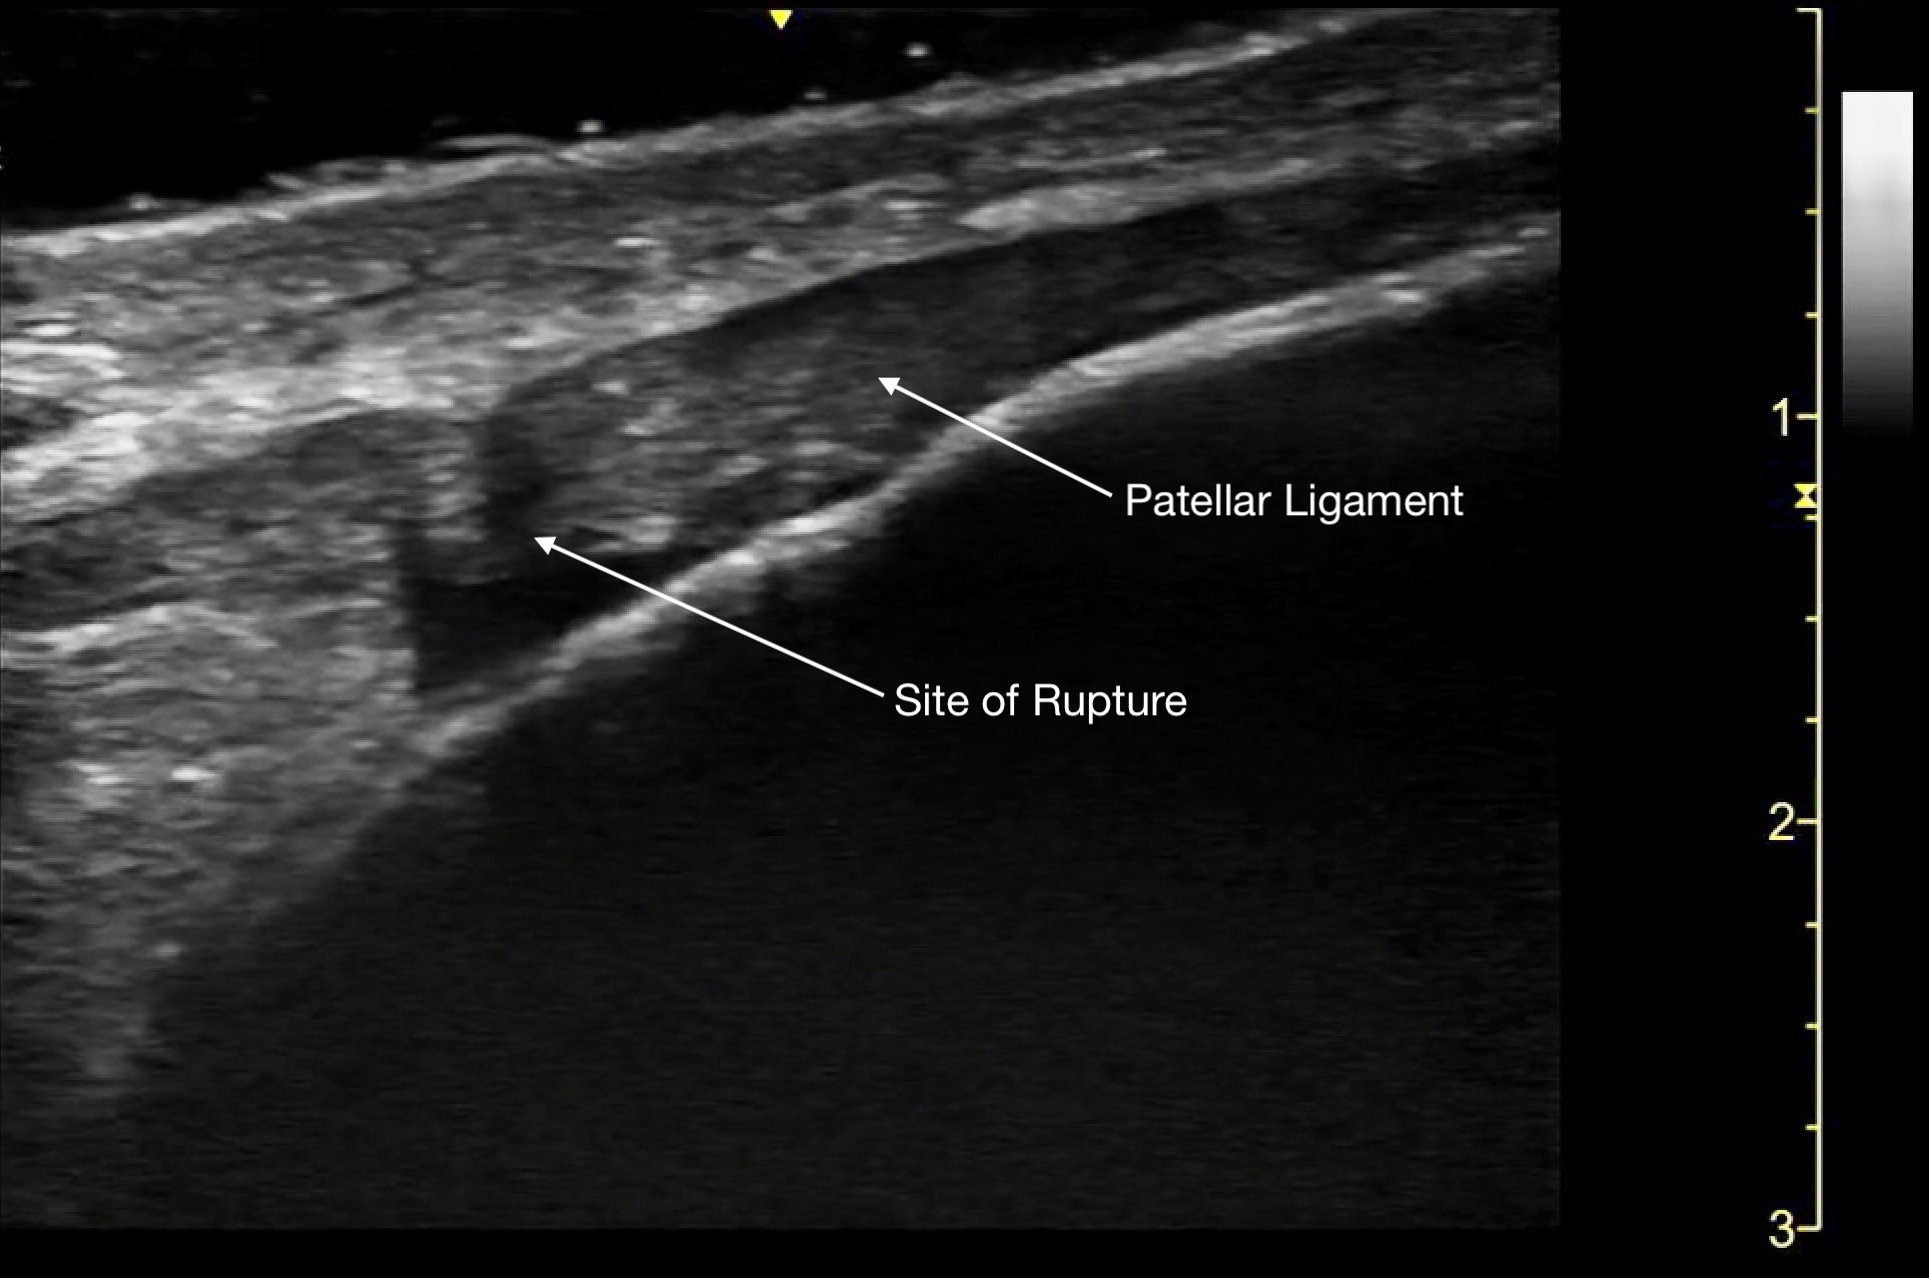

Tendon ruptures appear as areas of hypoechogenicity from edema/hematoma, and adjacent bunched up, retracted tendon fibers. For complete tears, the portion of the tendon near the injury will lose its rigid, straight appearance and instead appear irregular and have a large gap between the torn end and its insertion point. Partial tears are more subtle and will sometimes only have a small, cone-shaped hypoechoic focus. The key with tendon exams is to view them dynamically, having the patient flex and extend the injured joint (if possible).

Figure 13a.

A) Partial rupture of the patellar ligament at the distal insertion

Video 10.

Partial rupture of the patellar ligament at the distal insertion, demonstrating the remaining intact portion when fanning across the ligament.